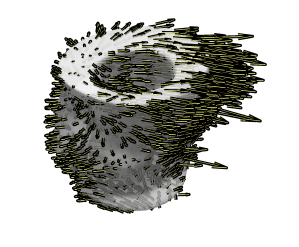

Fig. 5 demonstrates a 3D visualisation of the 3D velocity field from a full stack of TPM at peak expansion (a) before translational motion compensation, (c) after before translational motion compensation with method 1 and (b) method 2. The 3D visualisation of the uncorrected stack shows a bias in the velocity field caused by translational velocity, whereas the corrected stacks look more balanced. This visualisation of results pictures the difference in the two methods: Method 1 yields a stack which looks overall more symmetric as correction has been applied slice by slice taking into account the centre of mass per slice. On the other hand method 2 yields a stack where the base seems to move in opposite direction to the mid-wall and apex, revealing a relative motion between the lower and upper part of the LV. Visualisation of the second stack is looks more realistic and method 2 is recommended when examining deformation from the entire volume. When looking at deformation slice by slice method 1 yields more intuitive results and it is recommended in that case.